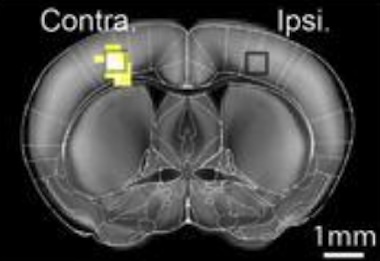

In trials studying stimulus-evoked brain responses in mice, HyFMRI successfully recorded cell-type-specific calcium signaling alongside whole-brain hemodynamics, revealing new details of how astrocytes are involved in coupling neuronal activity to localized changes in blood flow.